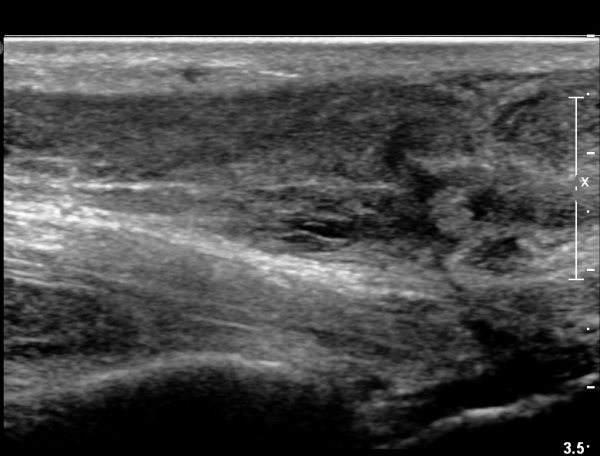

³»Ãø ºñº¹±Ù Á¾´Ü¸é°Ë»ç¿¡¼­ ³»Ãø ¹èº¹±Ù ¸»´ÜºÎ ÆÄ¿­°ú °¡Àڹ̱٠½ÉºÎ¿¡ ¼ö¾×Àú·ù°¡ °üÂûµÊ(»çÁø 1, 2).

¾ÆÅ³·¹½º°Ç Á¾´Ü¸é°Ë»ç¿¡¼­ ¾ÆÅ³·¹½º°Ç ¸»´ÜºÎ¿¡ ¾ÆÅ³·¹½º°ÇÀÇ Àú¿¡ÄÚºÎÁ¾, ±¹¼ÒÀû ¿¬°á¼º ¼Ò½Ç,

¹ß¸ñ°üÀý ÈĹæºÎ¿¡ ¼ö¾×Àú·ù°¡ °üÂûµÊ(»çÁø 3, 4, 5).